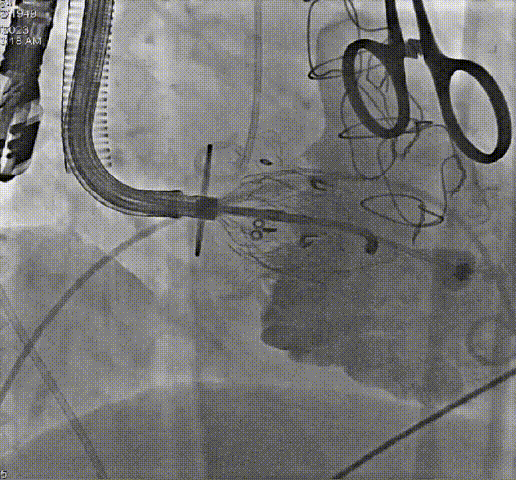

病例二

患者79岁,女性,“心房颤动”病史5年,近5个月出现活动时气促、双下肢水肿、乏力。“高血压”病史10年。心脏超声:极重度三尖瓣关闭不全,轻-中度二尖瓣关闭不全。TTVR术后三尖瓣关闭不全消失,轻微瓣周漏。

术前、术后造影结果